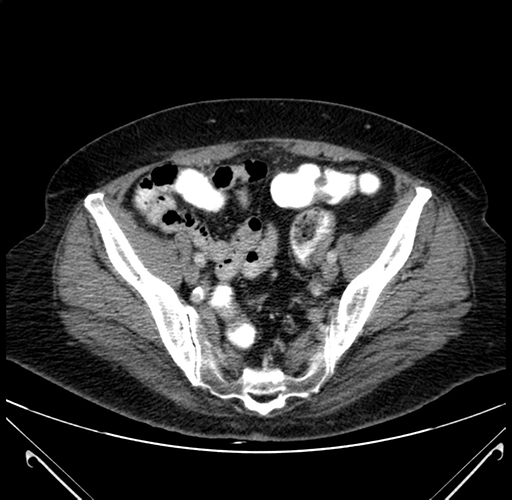

Look through the patient's CT scan to identify any areas of concern for the necessary procedure.

Based on your CT findings, which issue(s) would give reason for "planned slowing down moment(s)" in this case?

Considering a standard right hepatectomy procedure, what step(s) of the operation would you do differently in this case?